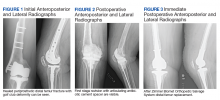

A patient with a history of hypertension, osteopenia, and rheumatoid arthritis underwent a primary right TKA in 2007. Ten weeks postoperatively, the patient had a ground-level fall that resulted in a right periprosthetic supracondylar distal femur fracture that was treated with a distal femur locking plate. The patient healed, however, with a significant golf club deformity (Figure 1). The patient did well for more than a decade but in 2019 was admitted with pelvic inflammatory disease and adnexal abscess that was treated with broad-spectrum IV antibiotics. Shortly after this admission, the patient developed a right knee periprosthetic infection with cultures positive for Ureaplasma parvum.

The patient then underwent a 2-stage revision of the infected TKA. Stage 1 consisted of explant of the TKA components as well as removal of the distal femur plate and screws and placement of an articulating antibiotic cement spacer (Figure 2). The patient completed 6 weeks of IV antibiotics. Following completion of the antibiotic course, we obtained a serum erythrocyte sedimentation rate, C-reactive protein level, and white blood cell count, which were all within normal limits. A knee aspiration was performed and did not show signs of residual infection. Frozen histopathology was sent during the second stage of the revision and did not show infection. After the results of the frozen histopathology returned, the antibiotic spacer was removed, and the femoral canal was thoroughly debrided. Cement and fibrous tissue in the femoral canal were carefully removed. In the setting of significant bone loss and soft tissue compromise due to the previous infection and distal femur fracture, the Zimmer Biomet Orthopedic Salvage System (OSS) with porous coated press-fit elliptical femoral stem was utilized.

The femoral canal was reamed until good cortical chatter was obtained at 16 mm. Per the Biomet OSS guide, “For bowed (curved) long and short press-fit stems, the final flexible reamer shaft diameter may need to be larger than the definitive trial and implant diameter.” After trialing, size 15.5 mm was selected for implantation. Intraoperatively the final stem was noted to have good interference fit after insertion and was stable throughout knee range of motion and varus/valgus stress testing. The patient did well with mobilization while in the hospital postoperatively and was discharged home (Figure 3).